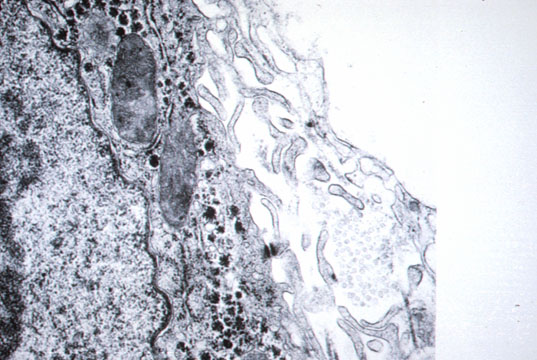

Lipocytes

Fig 19 - ITO CELLS (Lipocytes) They are perisinusoidal cells more frequent in zone 3. They have fat vacuoles and indented nuclei.Positive for desmin under immuno stain, especially on frozen sections. They store vitamin A and produce perisinusoidal reticulum. They become hyperplastic in hypervitaminosis A. Pitt cells Are hepatic Natural Killer cell present in rat liver sinusoids. They have a higher level of activation and different morphology than NK cells of the blood.They are large ,granular lymphocytes in contact with endothelial and Kupffer cells and can be identified with electron microscopy. Their role is probably a defence against viruses and tumors.

Reticulum

Fig 20 - RETICULUM:Stacks of collagen fibers in the Disse space.They stain black with silver impregnation.Is apparently produced by Ito cells.It forms the supporting framework of the hepatocytes.Its preservation in morbid conditions permits complete regeneration ad integrum while its destruction will produce scars,fibrosis and cirrhosis.